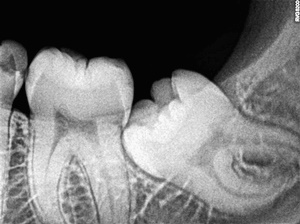

우리가 사랑니라고 부르는 것은 큰 어금니 중 세 번째 위치에서 제일 마지막에 나오는 치아입니다. 사랑니가 나올 때에는 첫사랑을 하듯이 아프다고 하여 붙여진 이름이라고 하는데요. 다른 이름으로는 ‘지치’라고 합니다. 지치는 사리를 분별할 수 있는 지혜가 생긴다는 뜻입니다.

사랑니는 보통 큰 어금니와 비슷하게 생겼습니다. 사랑니의 형태나 크기는 매우 다양하다고 하는데요. 보통의 어금니 보다 깊이 나기 때문에 빼기 어렵거나 절개를 통해 힘들게 빼야 하는 경우가 많습니다. 원래 사랑니는 음식물을 갈아 내기 위한 용도라고 하는데요. 이것은 치아의 퇴화 현상이라고 생각하시는 분들도 많이 계십니다.